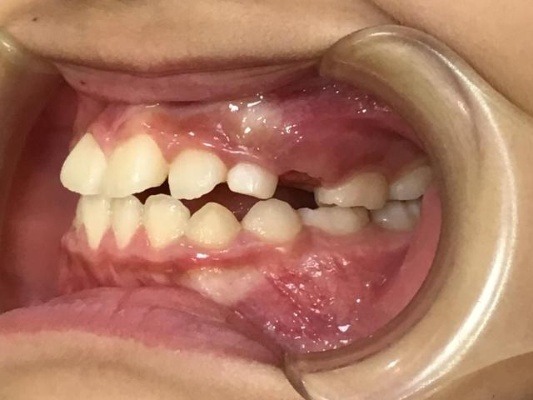

BEFORE

正面

右横

左横

| 治療内容 | インビザライン・ファースト |

| 治療詳細 | 叢生や交叉咬合を整えるために、歯の表面にアタッチメント(白い突起)をつけました。 |

| 主訴 | 歯のがたつき 一部分だけかみ合わせが反対 |